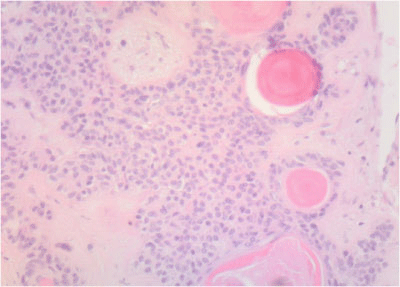

Final diagnosis: Cytopathologic study revealed a minor salivary gland tumor, with biphasic pattern and low prolipheration index with well defined borders and surrounded by a thick layer of fibrous tissue. Ki-67 prolipheration index <2%. Cytokeratin AE1/AE-3 was positive in the cellular areas and carcinoembryonic antigen (CEA) was negative demonstrating a PA with predominant cellular component (Figure 4). In this case multiple dilated thin-walled blood vessels filled with intraluminal deposits of eosin positive material were found leading to an intraoperative diagnosis of malignancy (Figure 5).

Figure 5 Intravascular deposits of cells and eosin positive myxoid material mimicking keratin nodules as described in some epidermoid carcinomas. Hematoxylin/eosin staining.